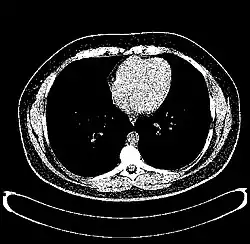

CT scan of the thorax with window level set to -700 HU (lung)

CT scan of the thorax with window level set to -1,000 HU (air)

CT scan of the thorax with window level set to 0 HU (water)

CT scan of the thorax with window level set to 60 HU (liver)